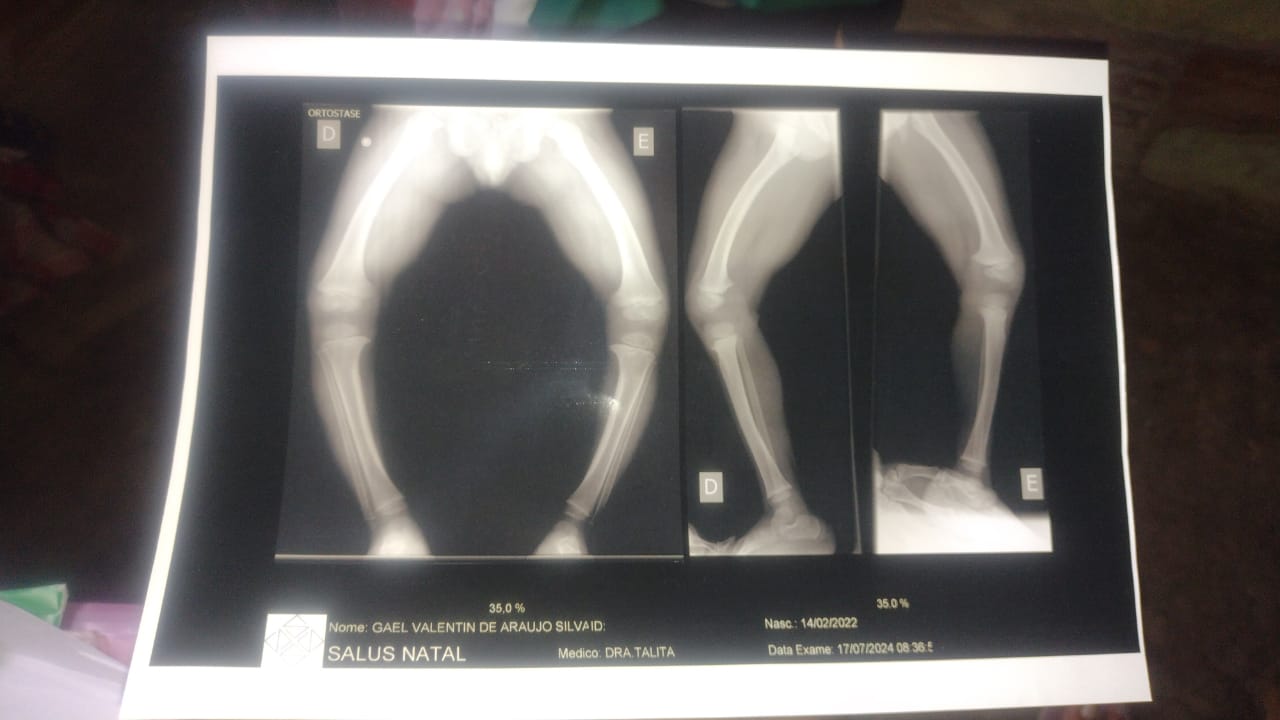

As.pernas do menino Gael estão cada vez mais abertas.

Gael , sofre desde do seu  nascimento de um problema nos  ossos de suas  pernas que dificulta o seu andar .

A família relata que a situação da criança é crítica, e que estão no aguardo de uma cirurgia .